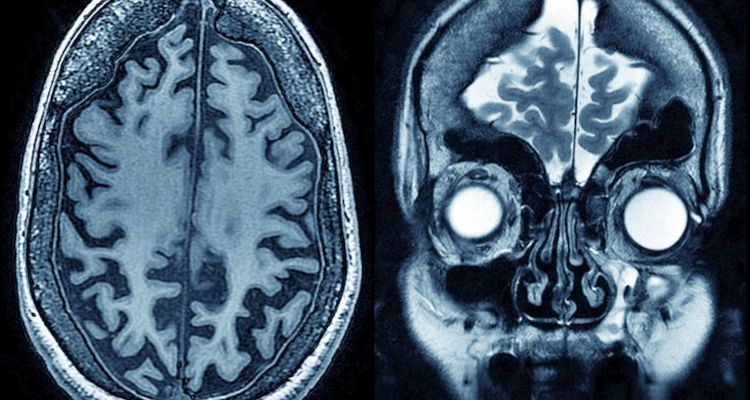

Une réflexion intense provoque une fatigue cognitive, se traduisant par la tendance à choisir des activités faciles et rapidement plaisantes. D’après une équipe française de recherche, cette fatigue est corrélée à une accumulation toxique de glutamate dans la zone du cerveau impliquée dans la prise de décision. Après une journée de travail et d’échanges sociaux, êtes-vous tenté-e de manger une pizza en regardant une série sur Netflix plutôt que de vous lancer dans la lecture de Proust? C’est tout à fait normal, réfléchir beaucoup entraîne une fatigue cognitive dans le cerveau, favorisant le choix d’activités faciles, agréables et sans attente. C’est ce que vient de démontrer une étude publiée ce jeudi dans la revue Current Biology.